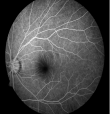

4.png

早期糖网-血管瘤样改变